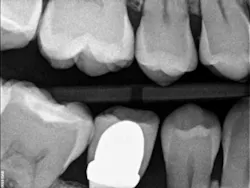

Recently, I changed my protocol for doing Class II dental restorations. I have started using indirect restorations more often. Depending on the size of the restoration, I now use indirect composites, inlays, onlays, and occasionally full-coverage crowns. Using indirect restorations allows one to control the emergence profile of the restoration and also ensures tight proximal and broad interproximal contacts. See Figures 3 through 6.

present at DL line angle not seen on radiograph.

food debris in the contact area.

embrasure space. Distal of No. 28 was restored as well;

not seen in this radiograph.